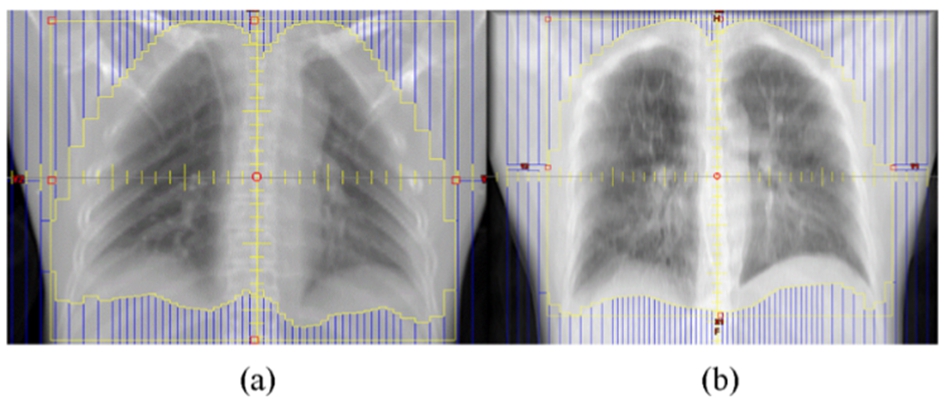

Detaliile realizarii radioterapiei cu doza

redusa sunt prezentate de echipa lui

Yuan din SUA in revista Physics and Imaging in Radiation Oncology, vol 11; pg

85-88, din luna octobrie 2020 si sunt reproduse in figura 5.

Figura 5.

Configuratia cimpului anterior al pacientului nr 7 si b) configuratia cimpului pacientului nr 6. Regiunile cu albastru marcate reprezinta delimitarea regiunii de protejat iar suprafata din interior reprezinta parenchimul pulmonar iradiat.